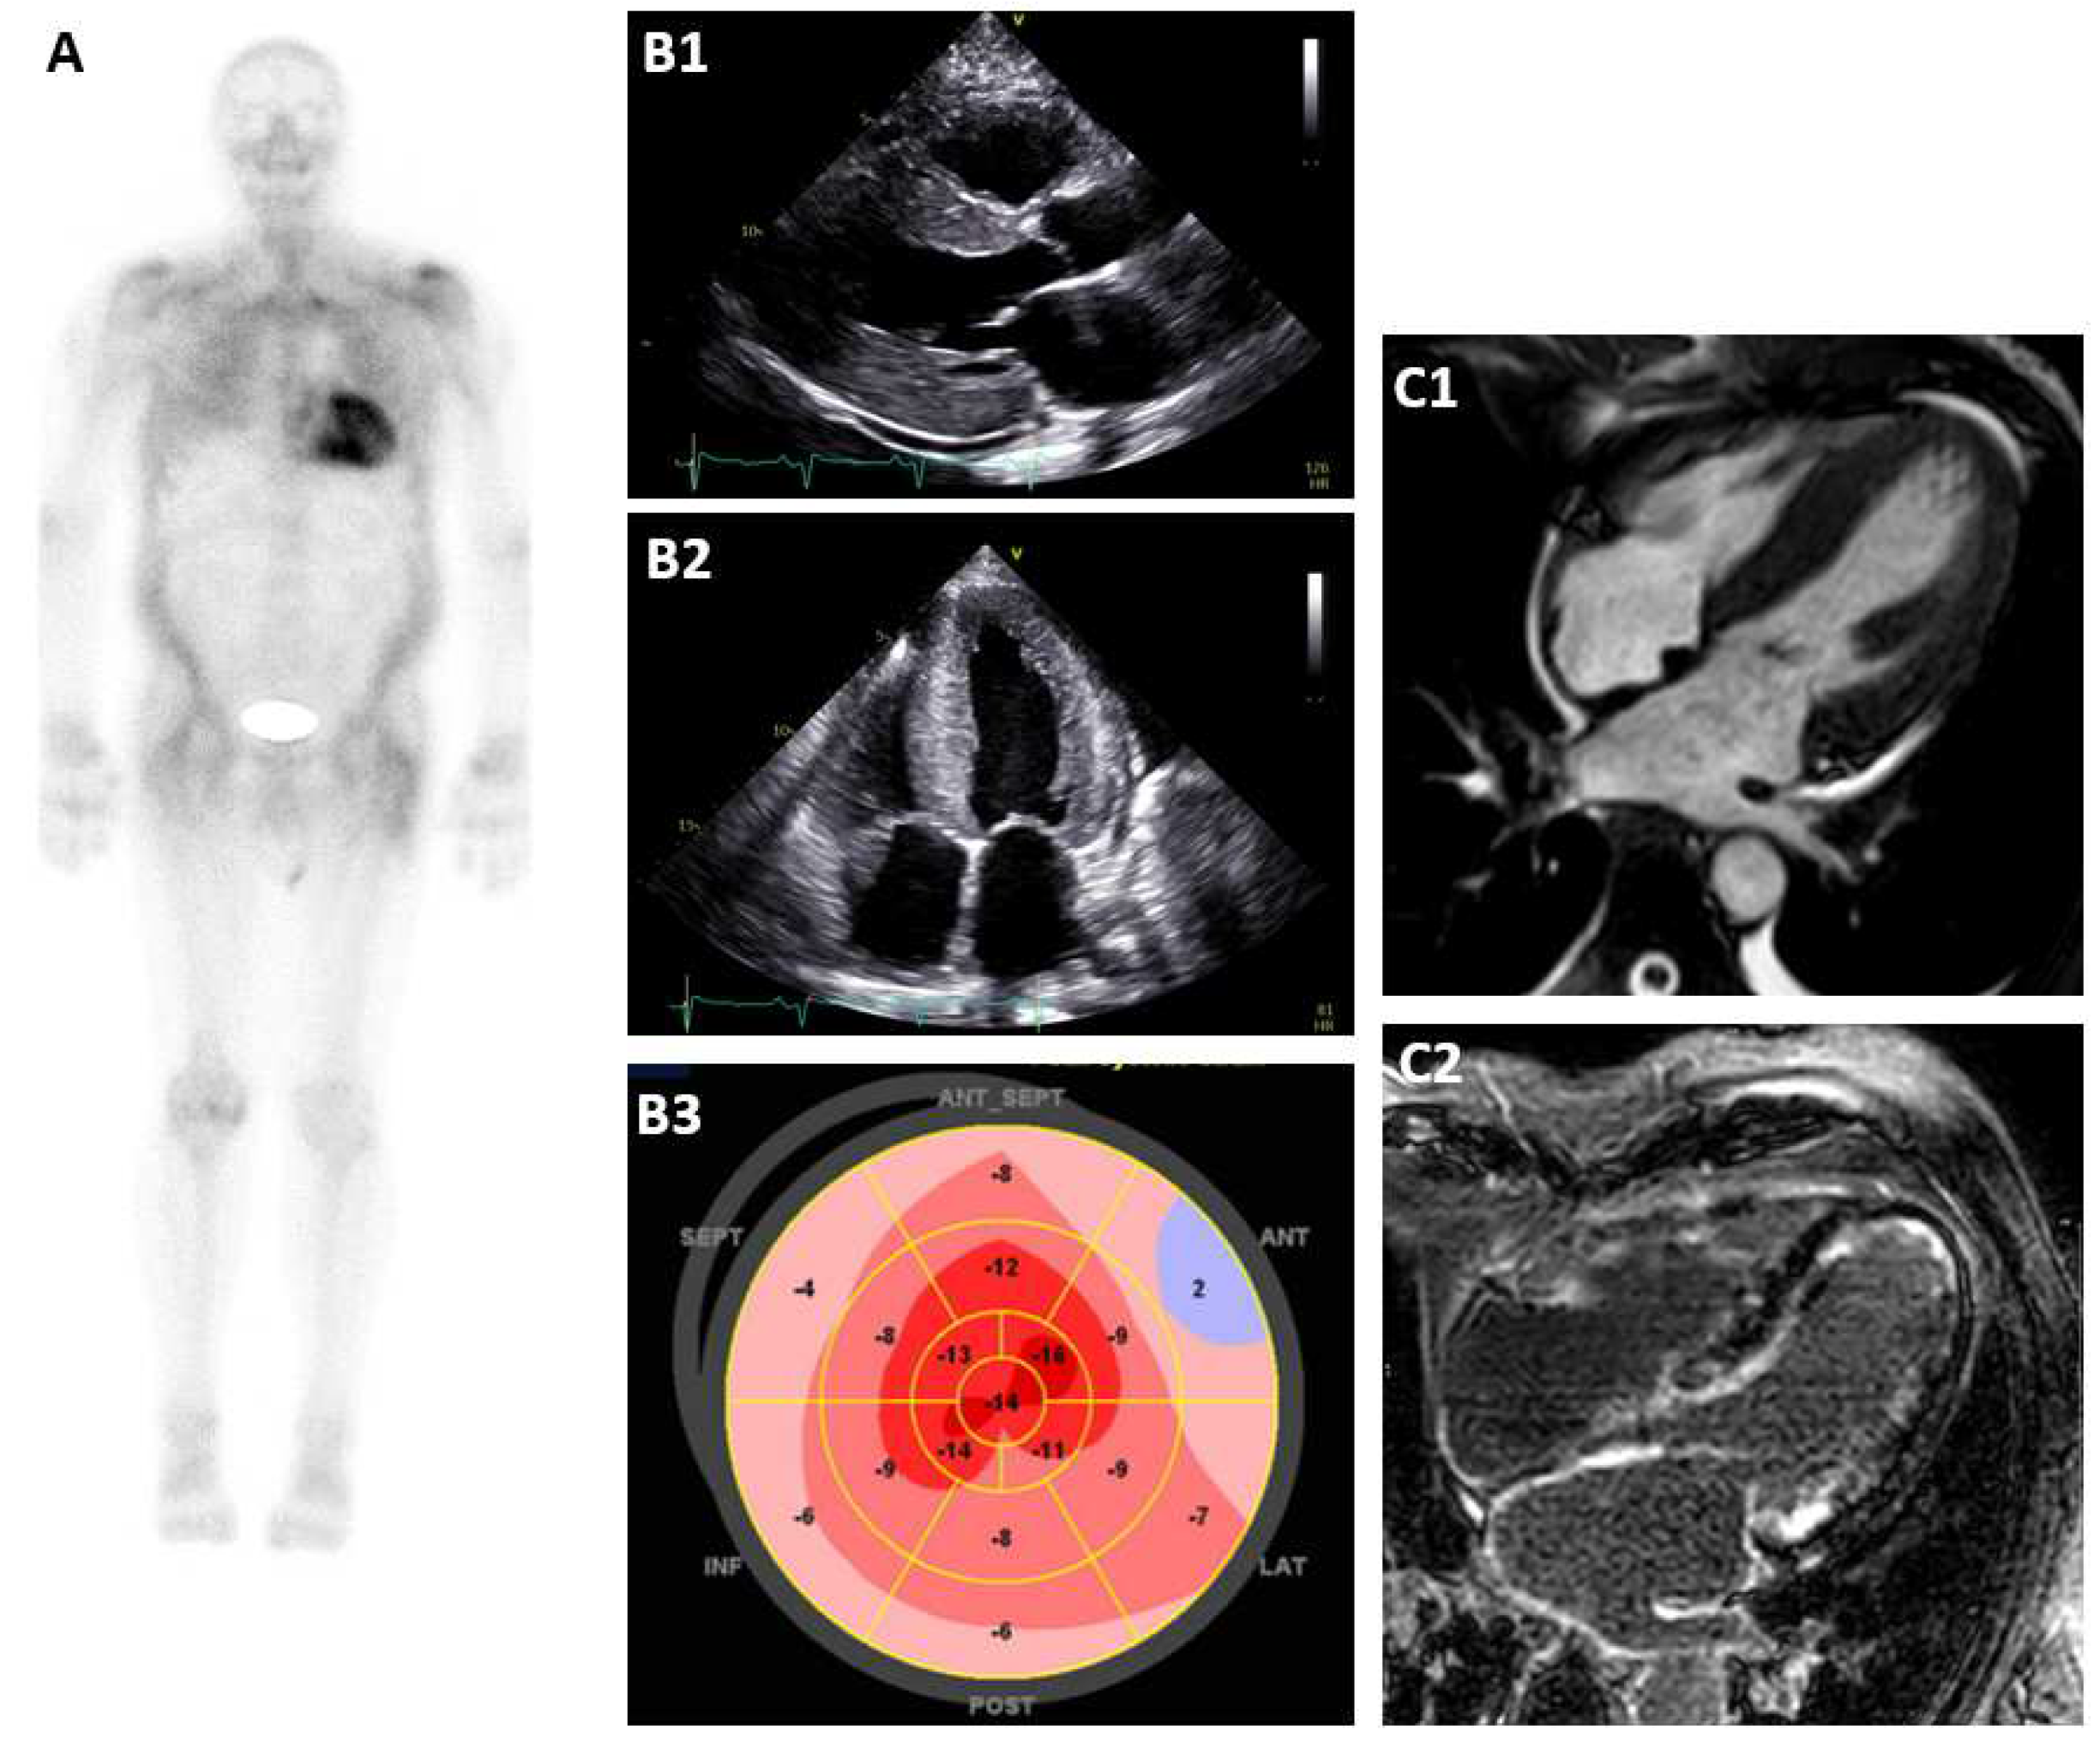

4. Echocardiography

5. Cardiac MRI

6. Bone Scintigraphy